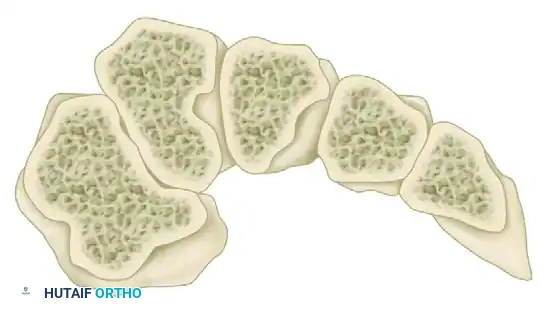

The Roman Arch and the Lisfranc Complex

The osseous architecture of the midfoot is inherently stable due to the trapezoidal shape of the cuneiforms and metatarsal bases, which form a transverse "Roman arch." The keystone of this arch is the base of the second metatarsal, which is recessed proximally between the medial and lateral cuneiforms, locking the complex in place.

FIGURE 84-14: Coronal section through the metatarsal bases illustrating the Roman arch configuration.